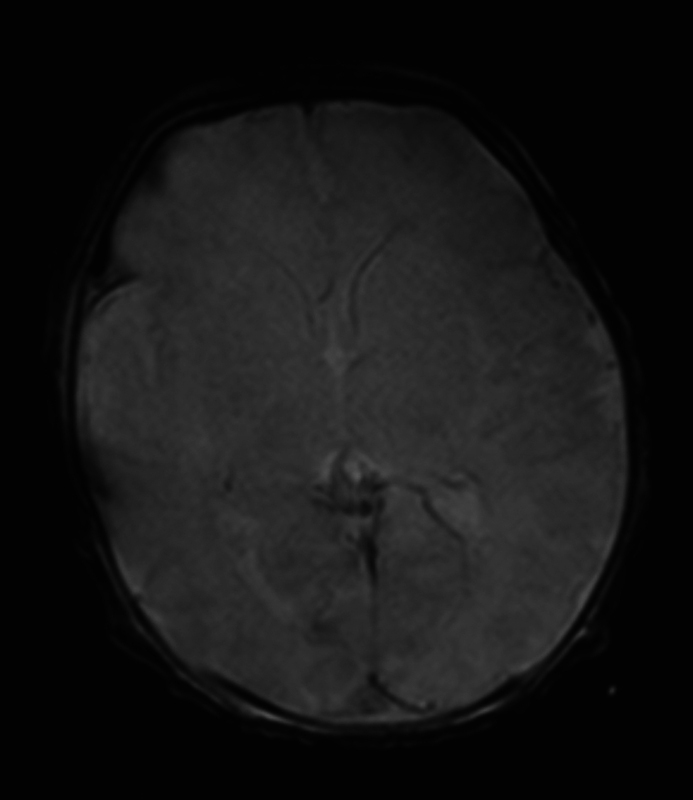

Background  Gestational alloimmune liver disease (GALD) is characterized by maternal IgG-directed fetal hepatocyte damage and can lead to severe liver failure and fetal or infant death. Moreover, GALD is associated with a near 90% risk of recurrence in subsequent pregnancies. Case  We present a case of a newborn patient delivered to a 32-year-old G2P1000 mother who received prolonged antenatal intravenous immunoglobulin (IVIG) treatment during the current pregnancy due to the neonatal death of the first child from GALD-related liver failure. Postnatal testing, including a liver magnetic resonance imaging (MRI) and buccal biopsy of this newborn, showed normal morphology of the liver without any abnormal iron deposition. Additional laboratory testing showed a lack of any liver injury. Conclusion  This case supports the use of antenatal IVIG immunotherapy to prevent the recurrence of GALD in subsequent pregnancies. Key Points GALD can lead to severe fetal liver injury.GALD is highly recurrent in subsequent pregnancies.Prophylactic IVIG may prevent GALD recurrence.

Abstract Image